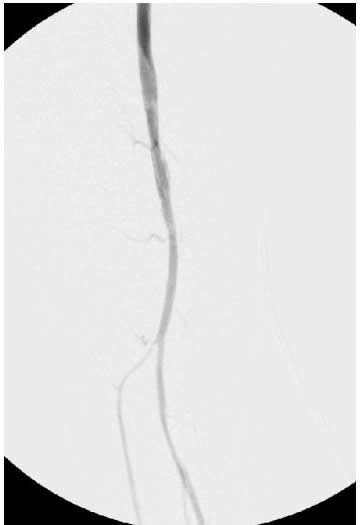

![]() |

Figure 1A: Angiogram |

Figure 1B: Following a day |

| Figure 1C: Angiogram shows restoration of limb perfusion. |

Case 1: An 84-year-old male with rest pain, who had undergone prior revascularization with covered stents, represents with recurrent rest pain. The prior stents had come close to the origin of the SFA and at that time there had been some narrowing. Exposure was provided by performing a cut down and patching the CFA-proximal SFA to the level of the stents, following which gentle thrombectomy was performed, and a wire passed down. The angiogram demonstrated a distal lesion at the adductor canal which contributed to the thrombosis (Figure 1A). The patient underwent a day of lysis, following which cryoablation was used to treat the distal lesion (Figure 1B) and completion angiogram showed restoration of limb perfusion (Figure 1C).